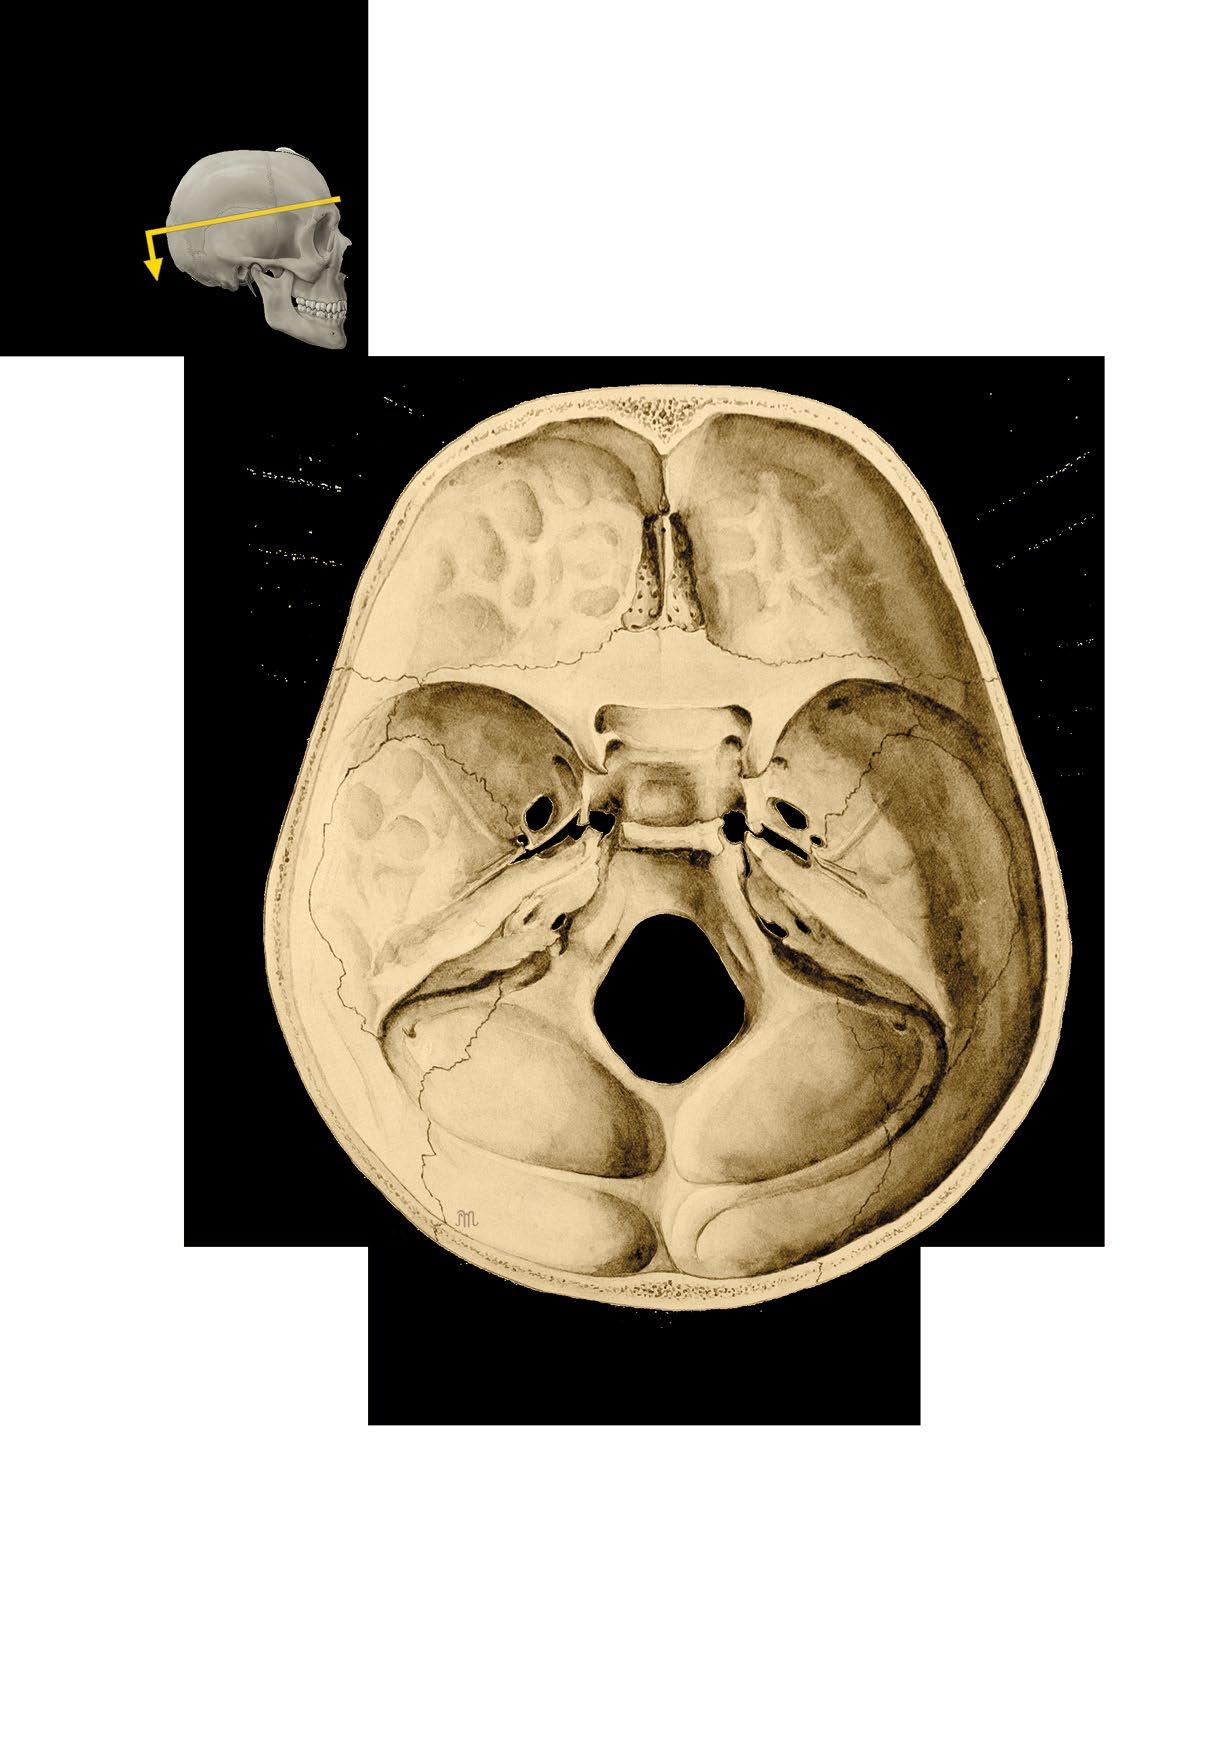

Basis cranii externa et interna

a zevní plocha base lební

b vnitřní plocha base lební

c členění vnitřní plochy base

fossa cranii posterior

External and internal base of the skull

a external surface

b internal surface c cranial fossae

canalis opticus impressiones gyrorum foramen rotundum

ala major

foramen ovale

foramen lacerum

foramen spinosum

apertura interna canalis carotici

meatus acusticus internus

foramen jugulare

canalis nervi hypoglossi

foramen magnum

pars orbitalis ossis frontalis ala minor

sulcus praechiasmaticus

processus clinoideus anterior

fossa hypophysialis processus clinoideus posterior

clivus dorsum sellae

margo superior partis petrosae

sulcus sinus sigmoidei

sulcus sinus transversi

fossa cerebellaris

protuberantia occipitalis interna

fossa cerebralis

Basis cranii interna, vnitřní plocha spodiny lebeční

Internal surface of the base of the skull